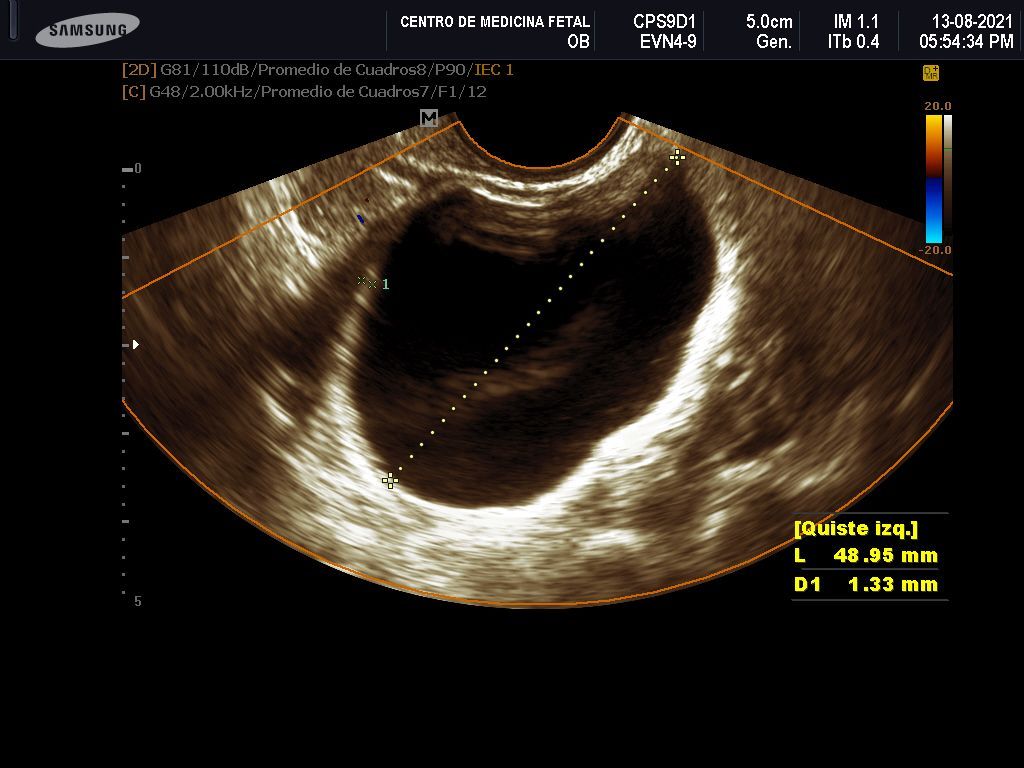

- Detección ecográfica transvaginal o pélvica y tratamiento de: Miomas, quistes de ovario, endometriosis, malformaciones uterinas